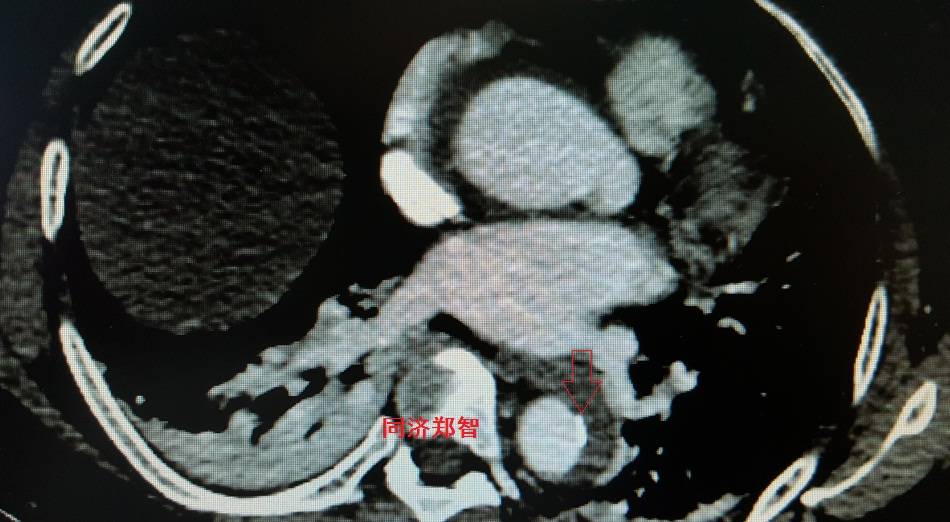

病例九

平扫CT提示降主动脉内膜片征,同时内膜片中可见一钙化点。CTA证实为B型主动脉夹层。